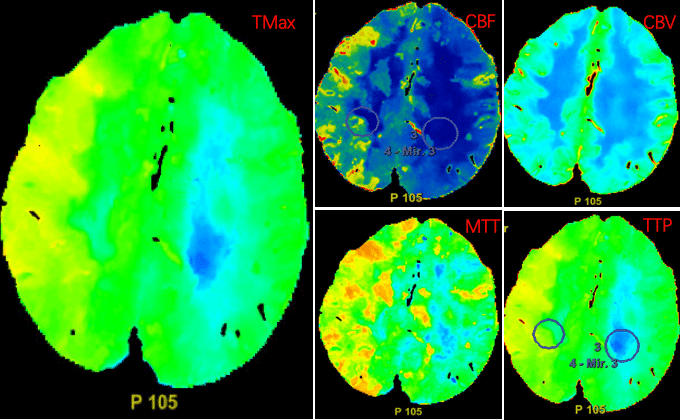

CTP显示双侧大脑半球灌注不对称:TMAX图示左侧大脑半球见片状蓝色及浅绿色区域,提示患侧达峰时间延长,AV=7.562s(健侧AV=5.156s);TTP图示左侧大脑半球见片状浅绿色区域,提示患侧达峰时间延长,AV=18.82s(健侧AV=15.19s);MTT图示左侧大脑半球见片状蓝绿色区域,提示患侧血流通过时间延长,AV=10.30s(健侧AV=6.651s);rCBV图示双侧大脑半球伪彩标记基本对称,AV=1.648ml(健侧AV=1.709ml);rCBF图示左侧大脑半球见片状蓝色区域,提示患侧局部脑血流量减少,AV=10.60ml/(100g.min)[健侧AV=19.19ml/(100g.min)]。